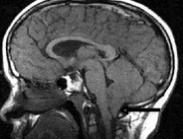

高免疫球蛋白E綜合征即Job綜合征,又稱姚皮炎綜合征、慢性肉芽腫病變異型(Granulomatous disease variant)、Buckley綜合征等。本病征是一種病因及發病機理尚不清楚的少見疾病。